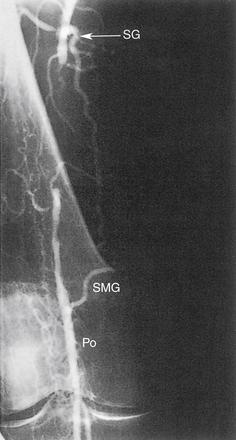

5. Обструкция поверхностной бедренной или подколенной артерии.а. Коллатеральный кровоток из глубокой бедренной артерии в дистальную поверхностную бедренную артерию или в подколенную артерию.б. Коллатеральный кровоток из дистальной поверхностной бедренной артерии в подколенную артерию или в проксимальные трифуркационные сосуды голени.в. Коллатеральный кровоток от проксимальной к дистальной подколенной артерии и/или подколенной артерии к трифуркационным сосудам

РИСУНОК 13-18. Окклюзию дистальной подколенной (Po) артерии можно обойти следующим образом: (1) икроножная (Su) и малая мышечная ветви → к возвратной передней большеберцовой артерии (rAT), которая кровоснабжает переднюю большеберцовую артерию (AT); (2) икроножная (Su) и малые мышечные ветви → к задней большеберцовой артерии (PT).